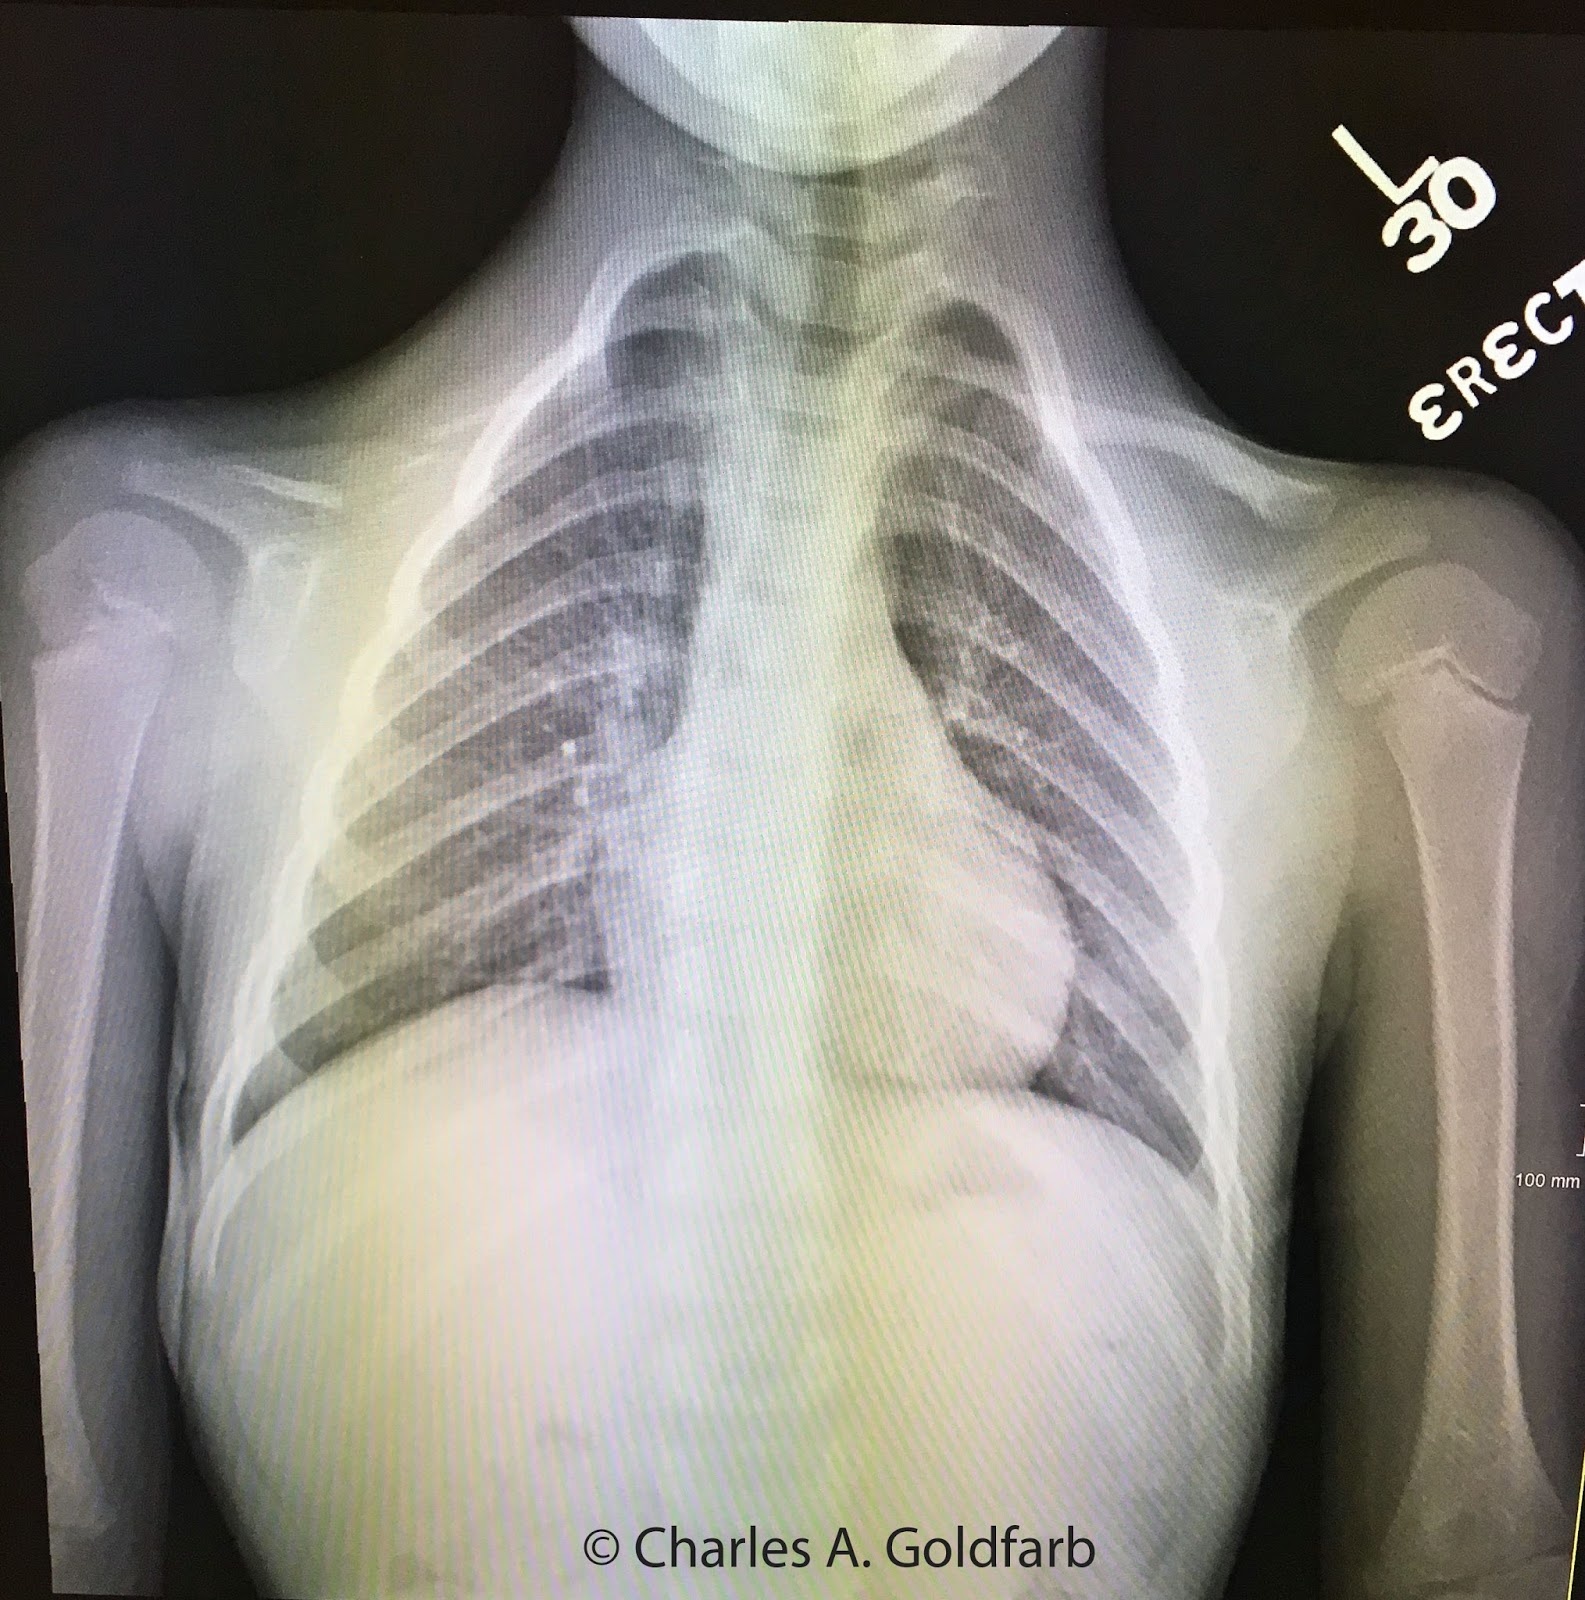

Hình ảnh chụp X-quang xương quai xanh của một bệnh nhân bị loạn sản xương sọ. Ảnh: Charles A. Goldfarb. |

Đặc trưng của người mắc chứng loạn sản xương sọ là tầm vóc ngắn, đường nét trên khuôn mặt có sự bất thường (trán nhô cao, khuôn mặt rộng bất thường, hàm trên nhỏ), vai hẹp, dốc do thiếu khuyết xương quai xanh. Ngoài ra, họ cũng gặp phải tình trạng khuyết hộp sọ (thóp), nắp sọ phình, xương chậu, xương mu, vùng lồng ngực biến dạng bất thường.